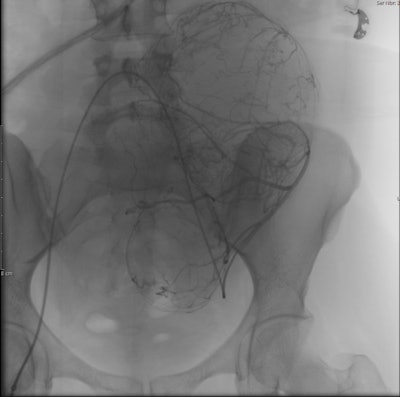

The minimally invasive interventional radiology procedure of uterine fibroid embolization (UFE) has a lower complication rate than myomectomy. It may be performed if a woman has a single fibroid, many fibroids, or large-sized fibroids and a gynecologist cannot rule out a hysterectomy during myomectomy, myomectomy is unsuccessful, or when fibroids recur after myomectomy. The procedure may also be performed for women who want to avoid surgical removal for culture reasons, surgically high-risk women with fibroids, women of any age with fibroids who want to preserve their uterus and avoid the psychological trauma of hysterectomy, and, more important, in unmarried virgin women with fibroids.

Uterine fibroid embolization blocks blood supply to treat painful uterine fibroids, and the procedure has a comparable fertility rate to myomectomy for women who want to conceive, according to what is thought to be the first study on the subject in the Middle East. The study was conducted by our group at Al Ain Hospital and presented ahead of print at the 2016 Arab Health Conference in Dubai, United Arab Emirates, in January and also presented at the Abu Dhabi annual gynecology conference in October 2015 and the Cleveland Clinic Abu Dhabi radiology conference in November 2015.

Premature menopause, hysterectomy, and radiation exposures have been identified as barriers to fertility when treating women with UFE, and they might occur with other known UFE complications in a very small number of patients, less than 4%. However, uterine fibroids themselves rarely cause infertility, but they may be a causative factor of pregnancy loss. The study participants were advised to wait six months or more after UFE before attempting to conceive, of which the reported time range before attempting to conceive was seven to 33 months (average 20 months).